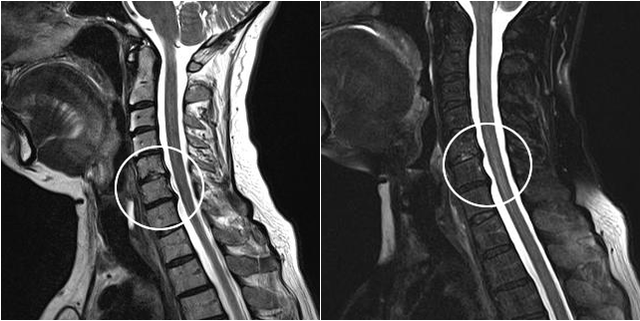

Les méthodes de diagnostic modernes incluent l'IRM et la tomodensitométrie, qui permettent d'examiner plus précisément les processus de destruction du cartilage et du tissu osseux. De plus, grâce à cette technique, il est pratique de diagnostiquer les hernies et autres défauts des tissus mous proches de l’origine de la maladie.